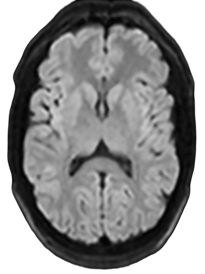

3D FLAIR

1.5T

1 x 1 x 3mm

3:31

0.5T

3:15